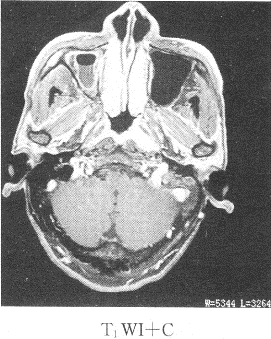

患者男性,39岁,因耳鸣,听力下降来院,影像学检查如图所示

1.该患者最有可能的诊断是

正确答案:1.C;2.B;3.ABDE 解题思路:鼻咽癌我国以广东省为高发地区,男性多于女性,好发于鼻咽顶壁,其次为侧壁,前壁和底壁极少。